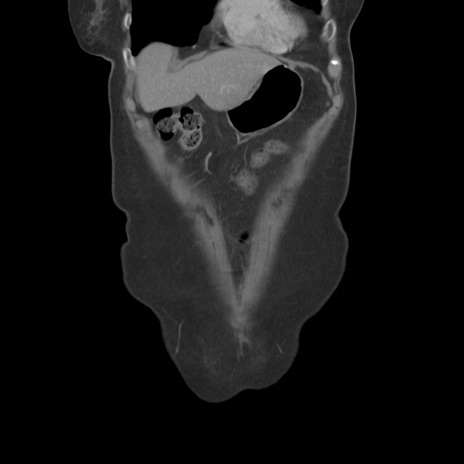

症例19(冠状断像)

【症例】80歳代女性

【主訴】下腹部痛

【現病歴】約8時間前より下腹部痛の出現あり、救急外来受診。

【既往歴】両側付属器切除

【身体所見】意識清明、下腹部正中に手術痕あり、その部位に一致して圧痛と反跳痛あり。腸蠕動音は亢進。

【データ】WBC 9300、CRP 0.15